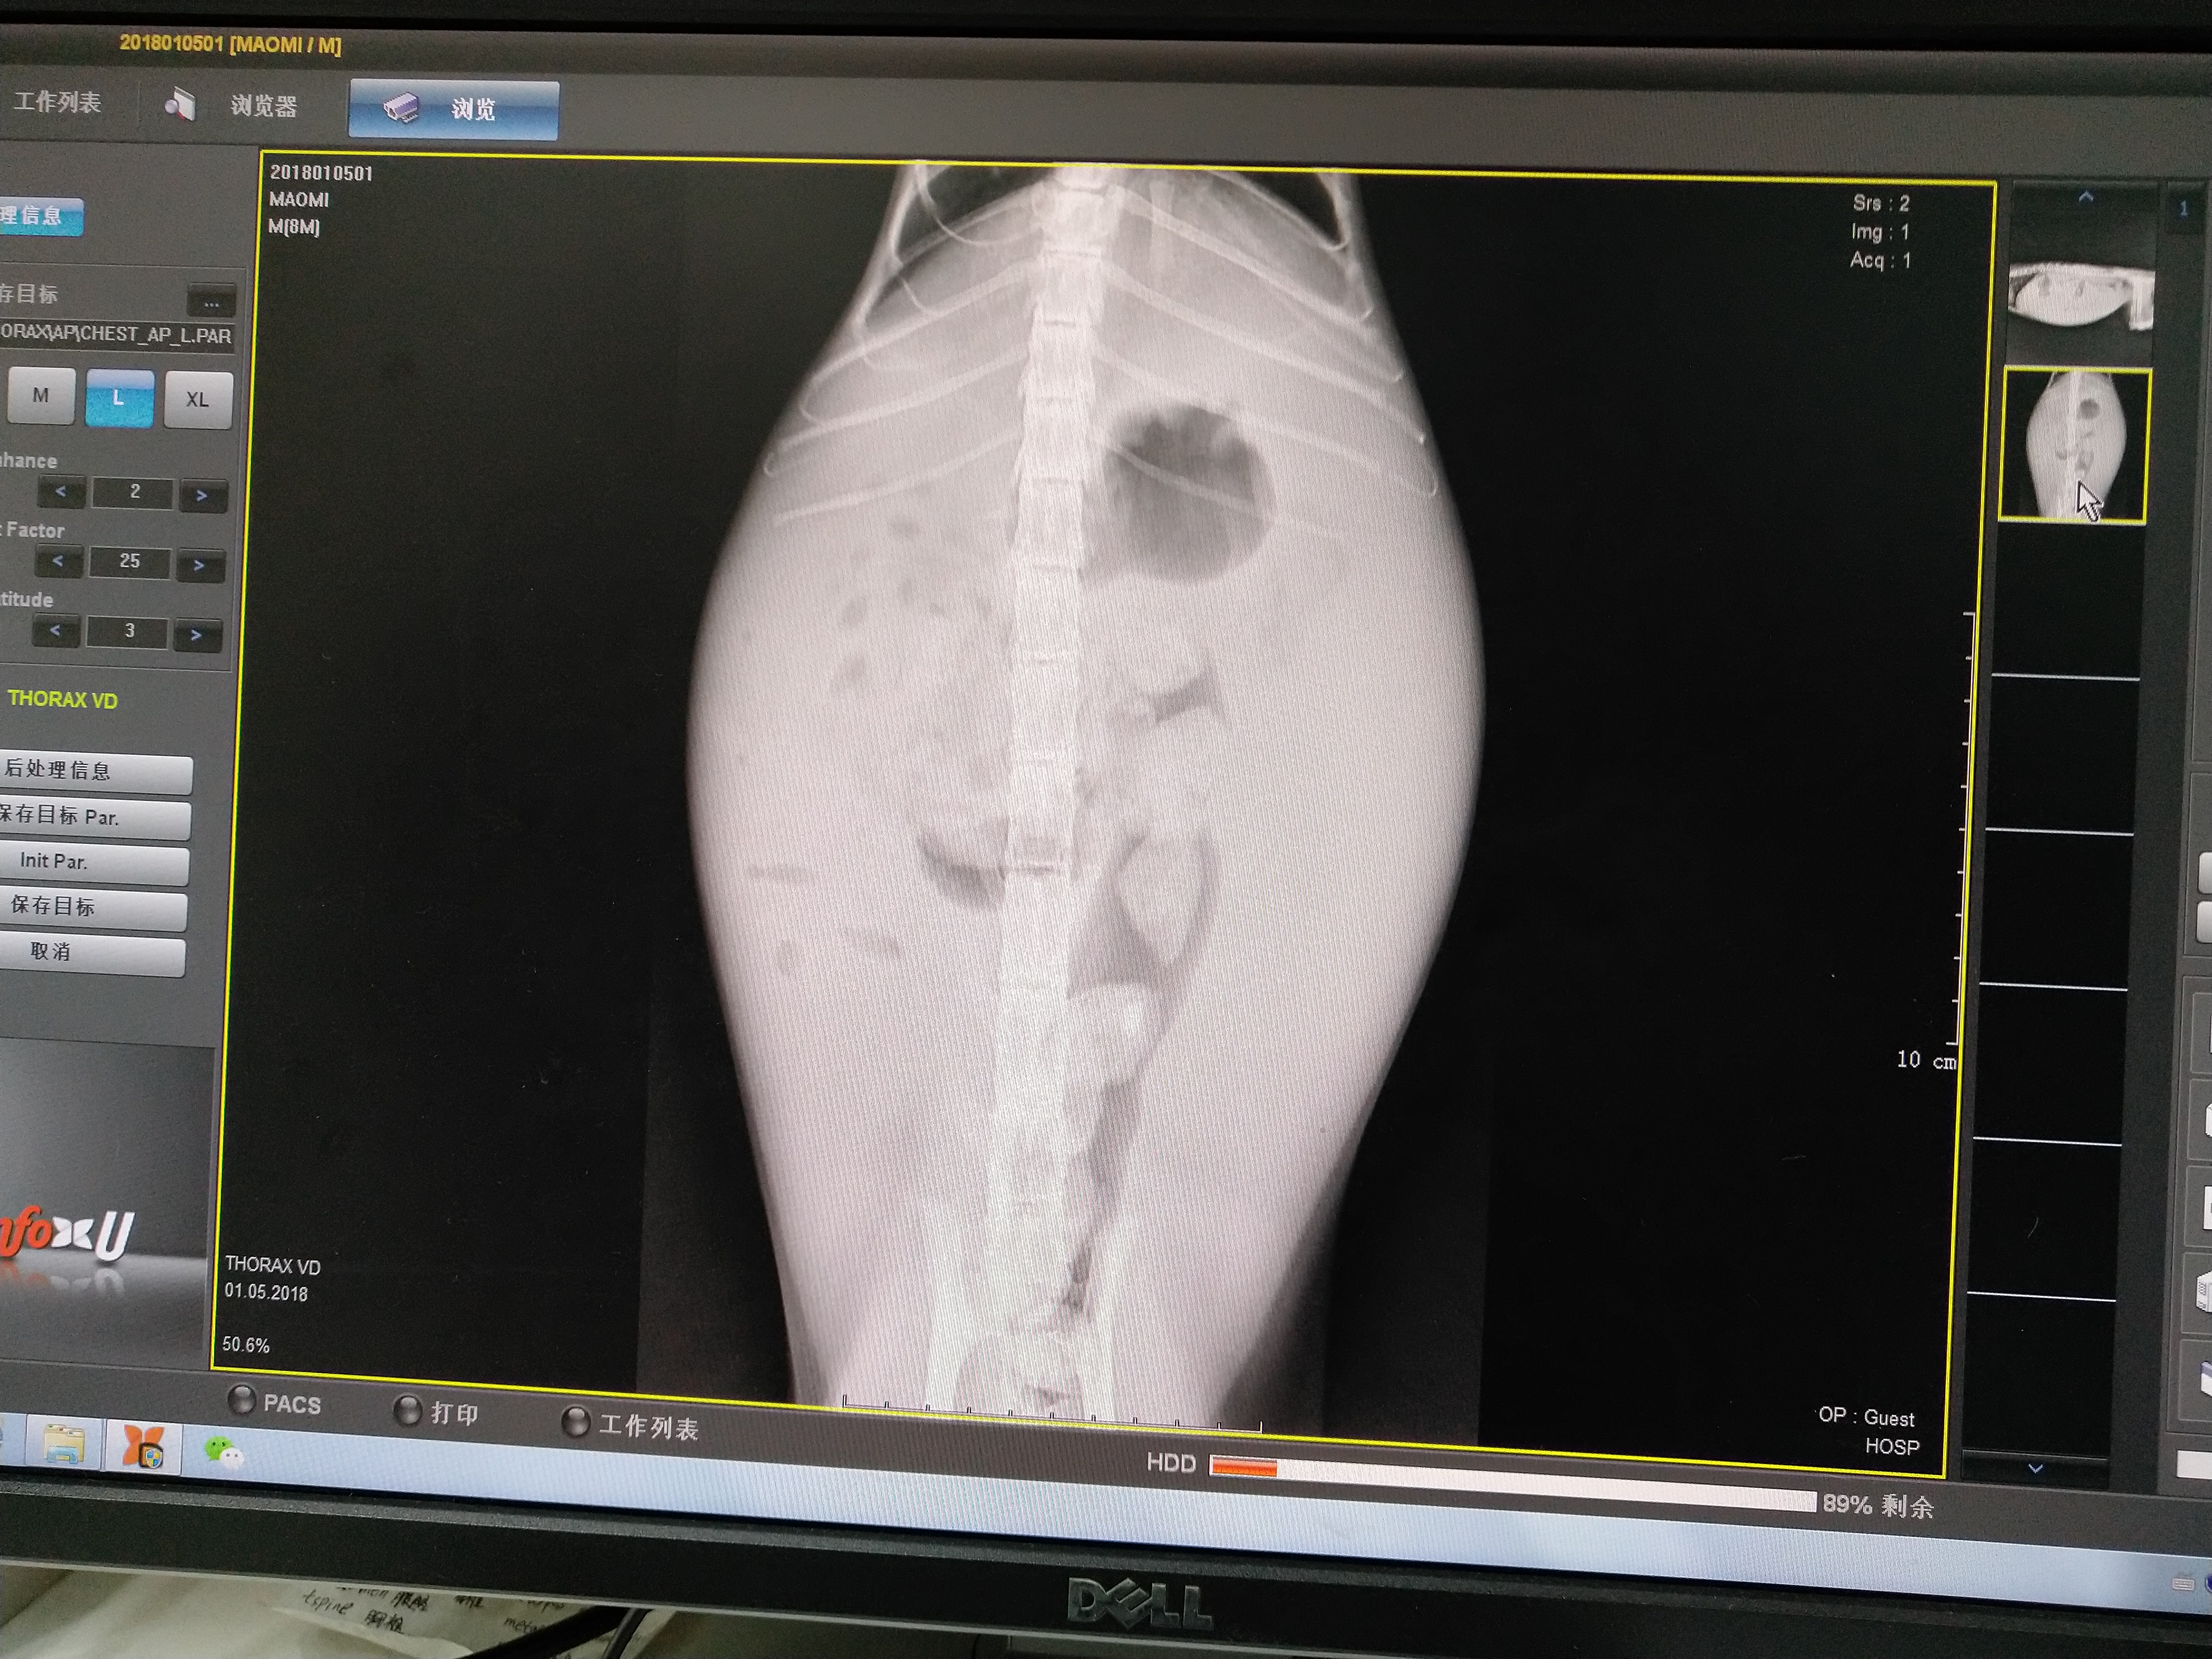

2.这个星期发现猫的肚子越来越大,脊梁骨突出,昨天五号带去福懋宠物医院检查了,做了血常规,生化,报告如下,医生口述肝脏受损,腹水多,血清呈黄色,正常呈无色。医生没有准确说是传腹还是肝腹水,只是说很难治愈。并且有黄疸